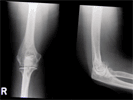

Pre

Op

56 year old Malay lady with rheummatiod arthritis with previous bilateral knee replacements done.Now,has pain and chronic swelling right elbow

X-rays elbow showing rheummatoid changes